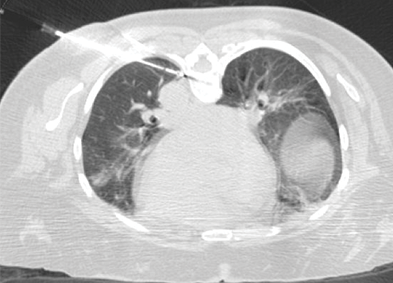

MRI top view of lung image MRI top view of lung image

Cryoablation of mCRC in the Lung Located Adjacent to the Aorta

A 57-year-old woman with a history of lung metastases from colorectal cancer presented with a new 1 cm lung metastasis identified in the lower left lobe. Cryoablation was performed with one IceSphere™ 1.5 needle and CO2 was injected into the pleural space to move the metastasis away from the aorta to prevent possible damage to the aorta and prevent the heat-sink effect that would reduce chances of complete ablation. The unique “stick-mode” feature offered by cryoablation allows the tumor to be moved away from vulnerable adjacent organs, and consequently for technically challenging lung tumors to be treated safely and effectively.

Thierry de Baere, MD I Gustave Roussy Cancer Institute I Villejuif, France